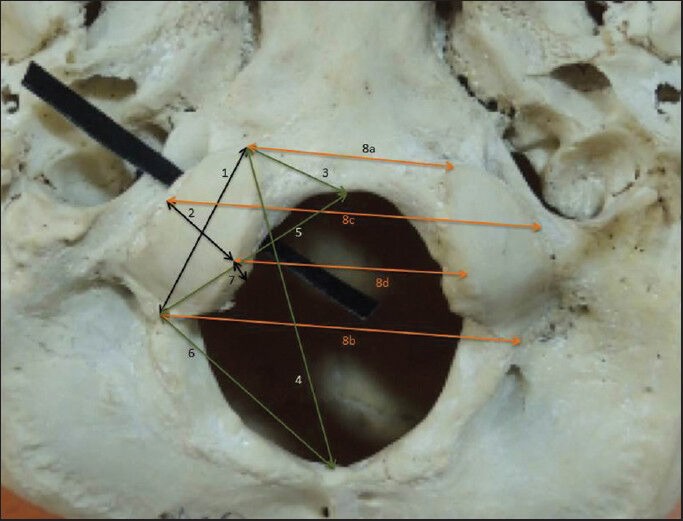

The study was performed on 142 OC of 71-adult human (55 male, 16 female) dry skulls. Metric and nonmetric study was performed in the collected specimens. The parameters examined for OC (bilaterally) were as below [Figures 1–3].

Figure 1.

Some metric parameters of occipital condyle (OC). (1) Length of OC. (2) Width of OC. (3) Distance between the anterior tip of OC and basion. (4) Distance between the anterior tip of OC and opisthion. (5) Distance between posterior tip of OC and basion. (6) Distance between posterior tip of OC and opisthion. (7) Thickness of OC. (8a) Anterior intercondylar distance. (8b) Posterior intercondylar distance. (8c) Bicondylar distance is lateral. (8d) Bicondylar distance medial